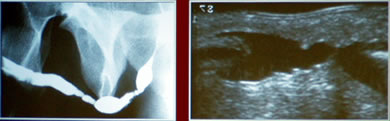

Заболевания

уретры, сопровождающееся стриктурами уретры

Двойная

Протяженная

После операции